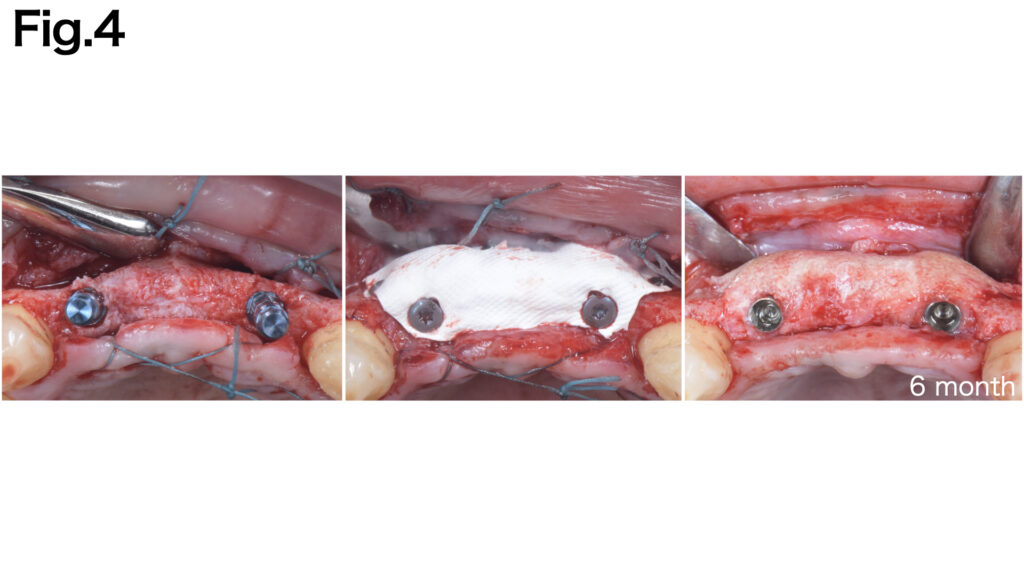

CASE 6 (Type V)

The vertical bone defect was identified. Fixation pins were applied to both the buccal and lingual aspects to achieve secure fixation of the titanium membrane (Ti-honeycomb membrane, TiHM). After six months of healing, adequate bone regeneration was achieved.